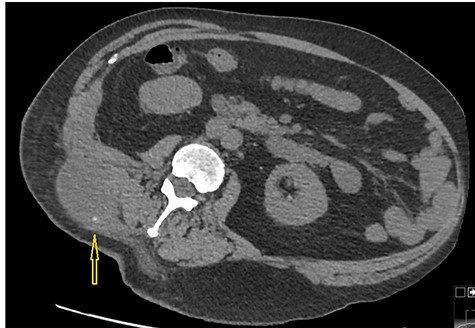

A CT scan abdomen was performed, which demonstrated a large retroperitoneal abscess behind the liver tracking through a small intramuscular opening onto the skin over the upper aspect of the back (Fig. 2).

Because of previously identified calcification in the mass lesion and history of laparoscopic cholecystectomy, a non-contrast CT scan abdomen was obtained to ascertain if spilled gallstones were responsible for the recurrent abscess formation (Fig. 3).

CT scan abdomen demonstrates a retroperitoneal abscess tracking through an intramuscular opening onto skin in the right paraspinal region.